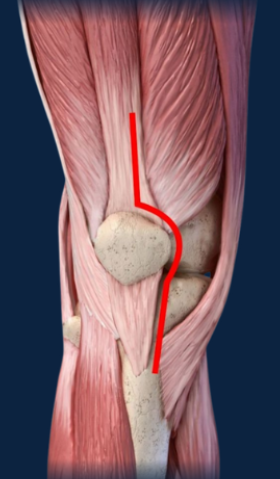

Cruciate retaining type of implants (fig 3) were used for all patients selected for the study and medial Parapatellar approach to knee (Fig 4) used in all cases. For closure Number 2 vicryl for the capsule and subcutaneous tissue and staples used for skin. Post-operative mobilization was started on post op day 2.

Figure 4